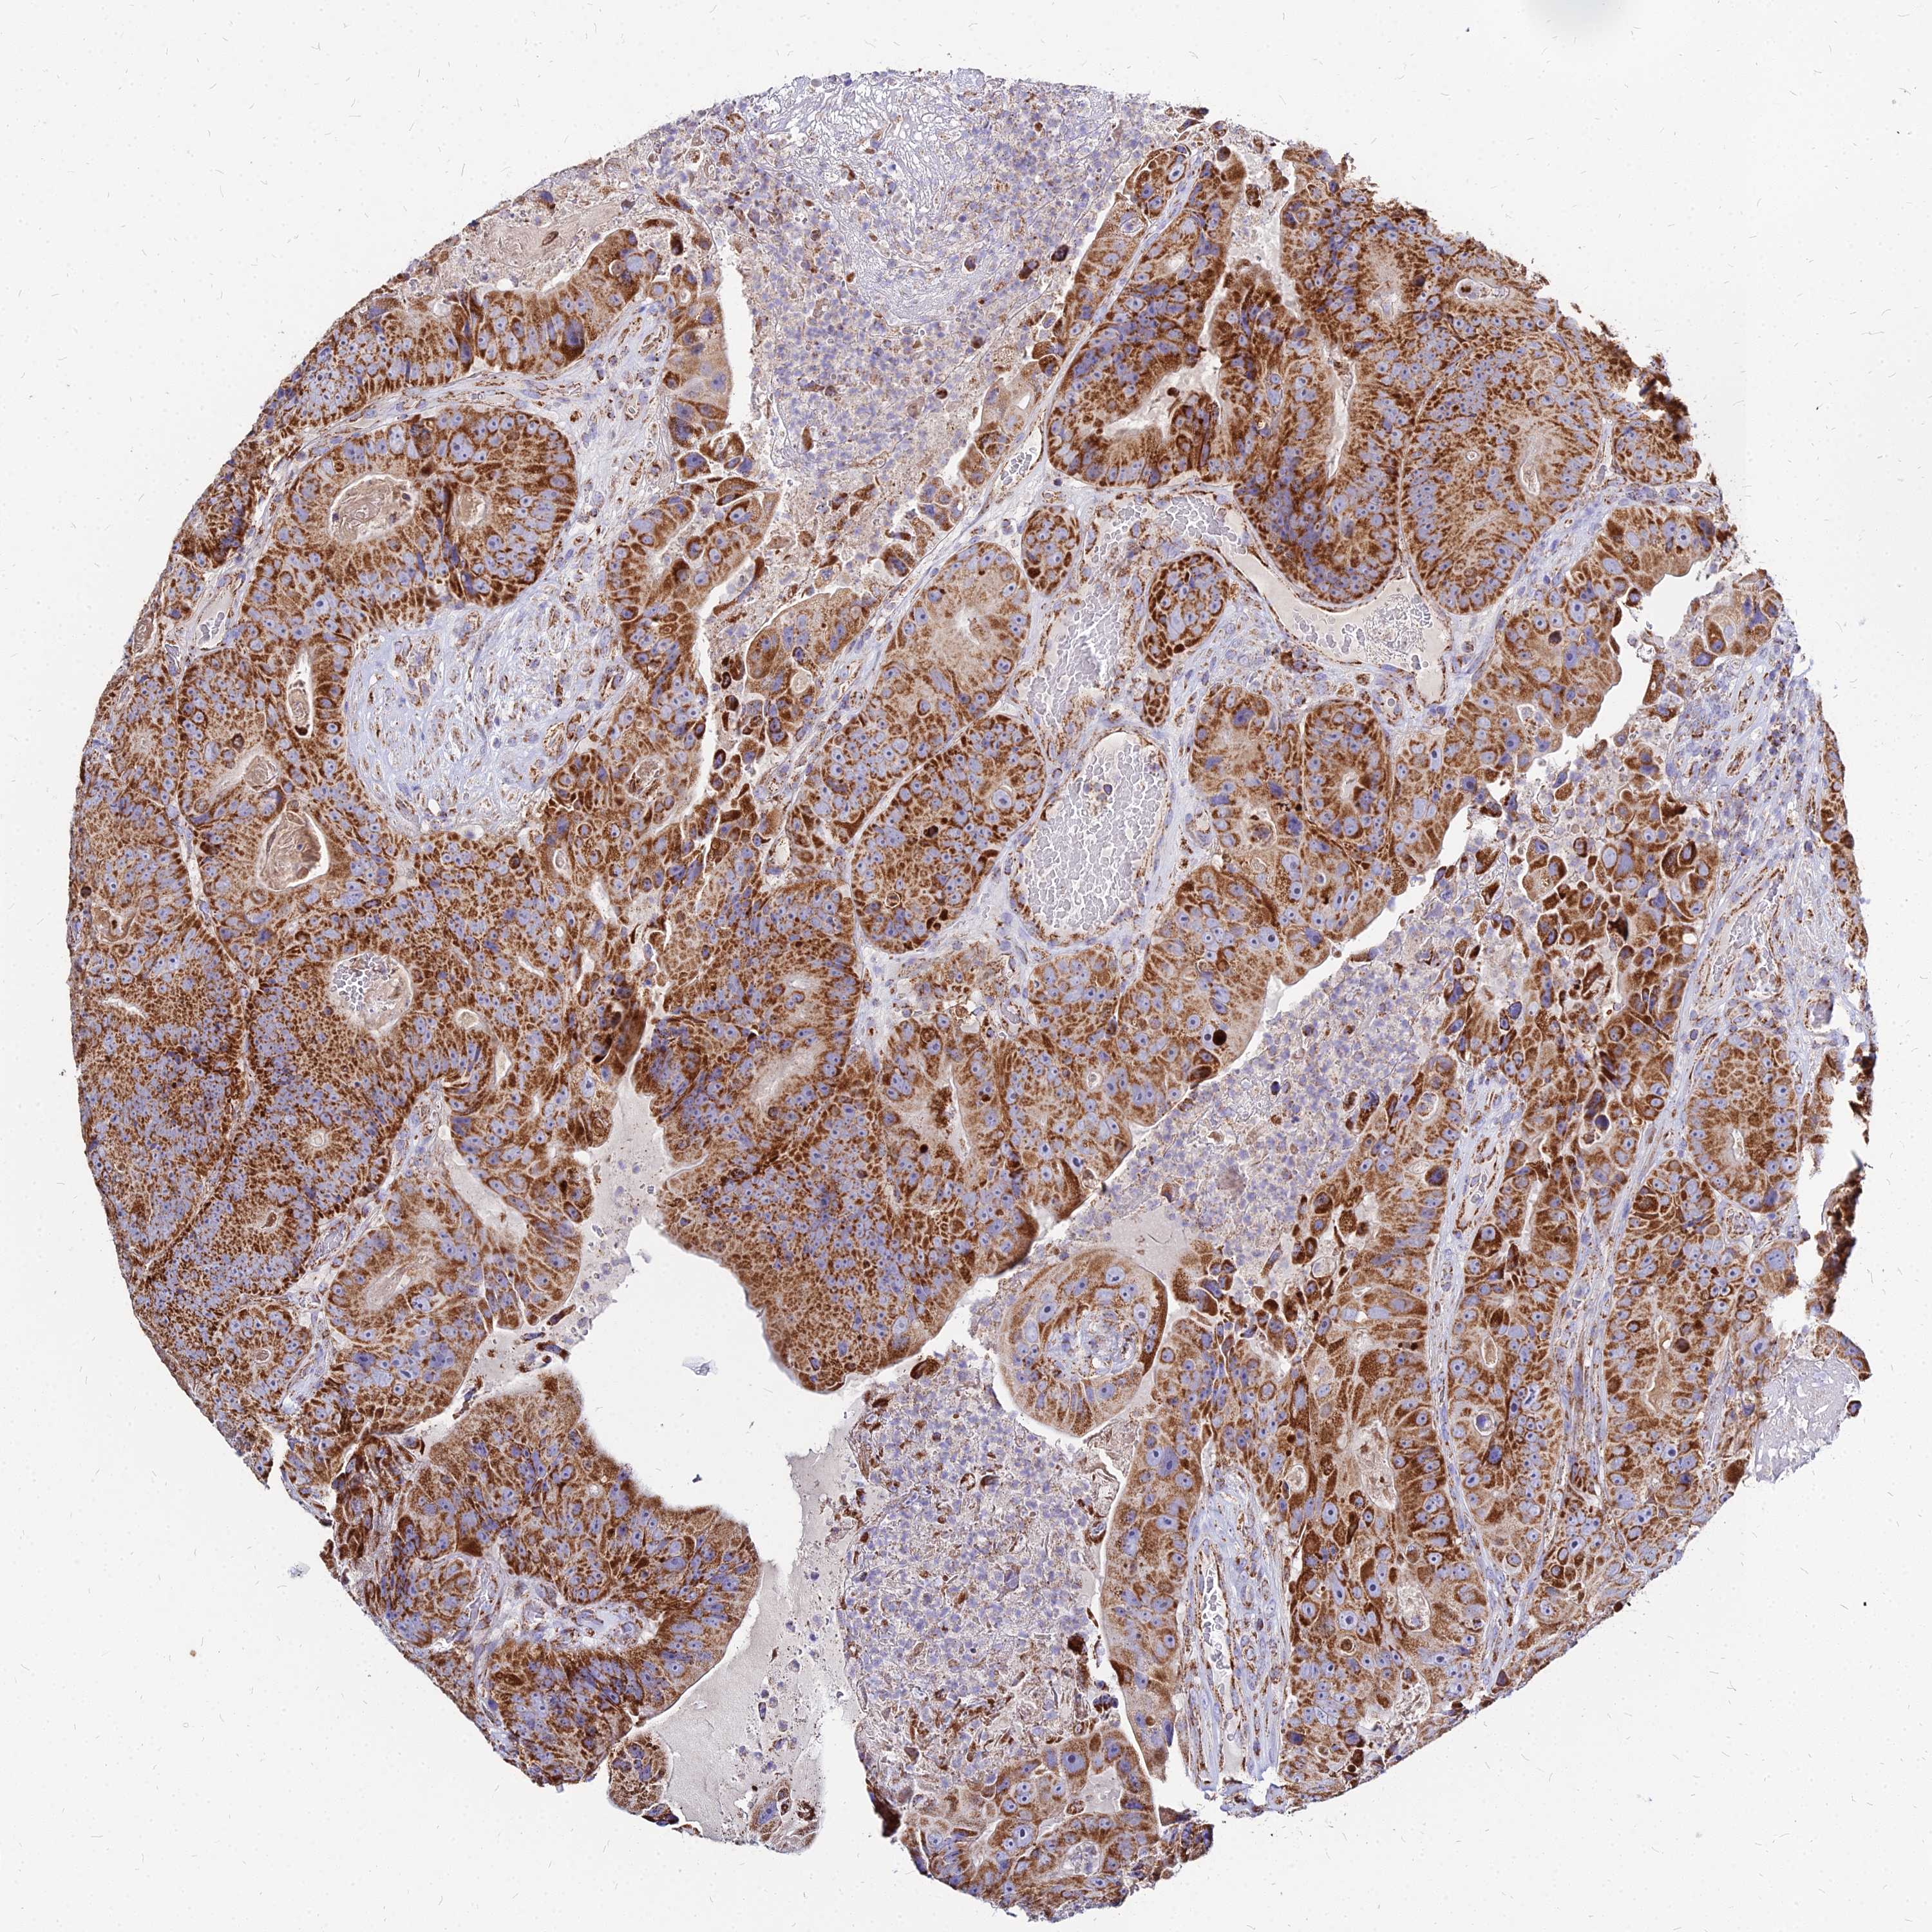

CANCER COLORECTAL CANCER Show tissue menu

Colorectal cancer

Human cancer

Colon adenocarcinoma